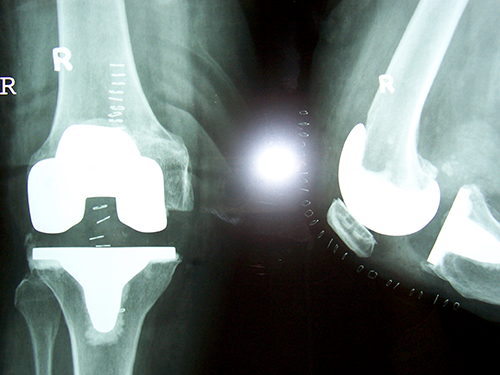

Case:1 TKR

Case:2 TKR

Arthroscopy Surgeon in Ahmedabad

Pre-Op AP

Pre-Op Lateral

Post-Op